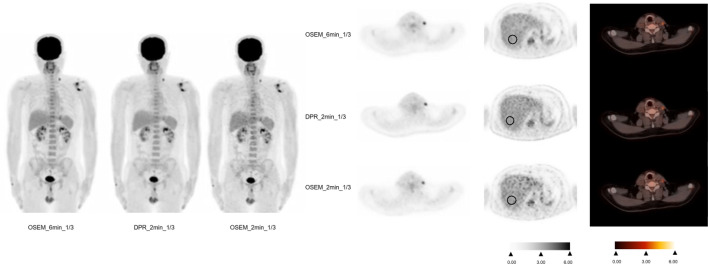

Methods: A total of 87 lymphoma patients (age, 45.1 ± 14.9 years) who underwent 18F-FDG PET imaging for during or post-treatment follow-up from November 2020 to February 2024 were prospectively enrolled. The patients were randomly assigned to two groups, including the 1/3 standard dose group and the standard dose group. Forty-four patients were injected with 1/3 standard dose (1.23 MBq/kg) and scanned for 6 min per bed and were reconstructed: ordered-subsets expectation maximization (OSEM) with 6 min per bed (OSEM_6 min_1/3), OSEM_2 min_1/3 and DPR_2 min_1/3. Forty-three patients were scanned according to the standard protocol (3.7 MBq/kg) and were reconstructed: OSEM with 2 min per bed (OSEM_2 min_full), OSEM_40 s_full and DPR_40 s_full. Additionally, the conventional 5-point scale measurement analysis was performed and DS for lymphoma were determined in different groups. Wilcoxon signed-rank test was used to compare the mean values of liver SUVmax and mediastinal blood pool (MBP) SUVmax in each group. Likert scale and DS were evaluated using Wilcoxon signed rank test.

Results: The patients with OSEM_6 min_1/3 and DPR_2 min_1/3 showed good image quality with 5(5,5) and 5(4,5) of Likert scoring, as well as the patients with OSEM_2 min_full and DPR_40 s_full. No significant difference was found between the OSEM_6 min_1/3 and DPR_2 min_1/3 groups in terms of liver SUVmax and MBP SUVmax (P = 0.452 and 0.430), as well as the patients with OSEM_2 min_full and DPR_40 s_full (P = 0.105 and 0.638). No significant difference was found between the OSEM_6 min_1/3 and DPR_2 min_1/3 groups in terms of lesion SUVmax (P = 0.080). There was a significant differences in lesion SUVmax between OSEM-2 min_full with DPR-40 s_full (P = 0.027). The DS results were consistent (100%) between OSEM-6 min_1/3 with DPR_2 min_1/3, and between OSEM-2 min_full with DPR-40 s_full, respectively.